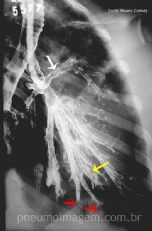

CASO CLÍNICO #36

A que tipo de tumor primário pertencem essas metástases no pulmão? Preste atenção às setas e deixe os seus comentários logo abaixo. ***** What is the primary tumor belonging to these lung metastases? Pay attention to the arrows and leave your comments be...